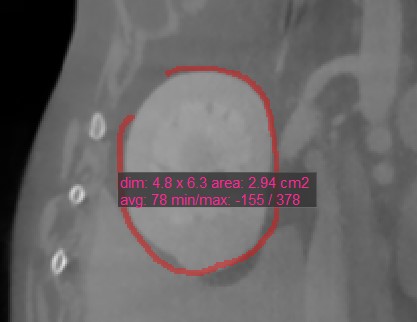

Oval¶

Select the Oval tool and assign it to one of the available mouse buttons. Start the measurement by pressing on the active image slice and drag the mouse to obtain an oval shape. Release the mouse when satisfied

with the size of the marked area.

All available measurement values are displayed alongside the measurement.

Modify the marked area by moving one of the four points describing the rectangle around the oval shape using the Default tool.